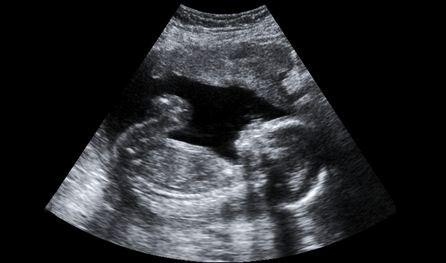

Minden leendő szülőt izgat a kérdés, hogyan is fejlődik a magzat az anya hasában. Nem véletlen, hogy annyira népszerűek az ultrahangos vizsgálatok, a „babamozik”: mindenki repesve várja, hogy bekukucskálhasson pár percre a külvilágról mit sem sejtő babához. Annyira kíváncsiak vagyunk, hogy akár hajlandóak lennénk hetente vizsgálatra menni, még akkor is, ha a szakemberek szerint erre semmi szükség, sőt.

Ezután teljes odaadással fordította figyelmét az emberi test működése, és azon belül is a várandósság fejlődése felé. Különleges, széles látószögű, makró objektívekkel és speciálisan átalakított endoszkópos műszerekkel felszerelkezve készítette el azt a fotósorozatát, amely aztán 1965-ben jelent meg „The Drama of Life Before Birth” címmel a Life magazinban. Még ugyanebben az évben megjelent a „Gyermek születik” című könyv is, amely azóta több kiadást is megért.

Négy évtized telt el, és az újra publikált könyv fotói mit sem vesztettek erejükből, varázslatukból. Az abortuszviták hevében is szinte mindig szóba kerülnek ezek a képek, hiszen világosan megmutatják, hogy az emberre jellemző vonások milyen hamar kialakulnak a magzaton. Mikor Nilssont megkérdezték arról, hogy véleménye szerint mikor kezdődik az élet a méhen belül, azt válaszolta, hogy az agysejtek már a harmadik héten kialakulnak – ám úgy gondolja, hogy erről mindenkinek meg kell hoznia saját döntését.